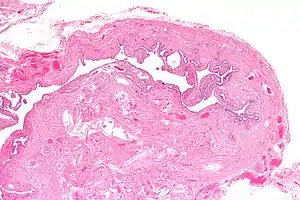

| Micrograph of salpingitis isthmica nodosa, showing the characteristic nodular thickening. H&E stain. | |

Salpingitis isthmica nodosa (SIN), also known as diverticulosis of the Fallopian tube, is nodular thickening of the narrow part of the uterine tube, due to inflammation.

It is characterized by nodular thickening of the tunica muscularis of the narrow (isthmic) portion of the Fallopian tube. In severe cases, it leads to complete obliteration of the tubal lumen. It is uncommonly bilateral.[2]